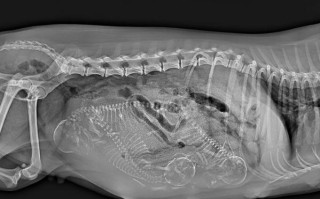

- 上行感染:如果在孕期发生感染,细菌有可能沿着阴道、宫颈向上蔓延,引发宫内感染,这可能会增加早产、胎膜早破或胎儿感染的风险。

- 强度未知:跳蛋带来的刺激强度远大于普通性生活,它可能导致更强烈、更频繁的子宫收缩,对于一些高风险孕妇(如有早产史、宫颈机能不全、前置胎盘等),这种强烈的刺激可能会诱发早产。

使用跳蛋时,如果插入过深或操作不当,可能会直接刺激到宫颈,宫颈的刺激是引发宫缩的另一个强效因素,在孕期,宫颈非常敏感,应尽量避免不必要的刺激。